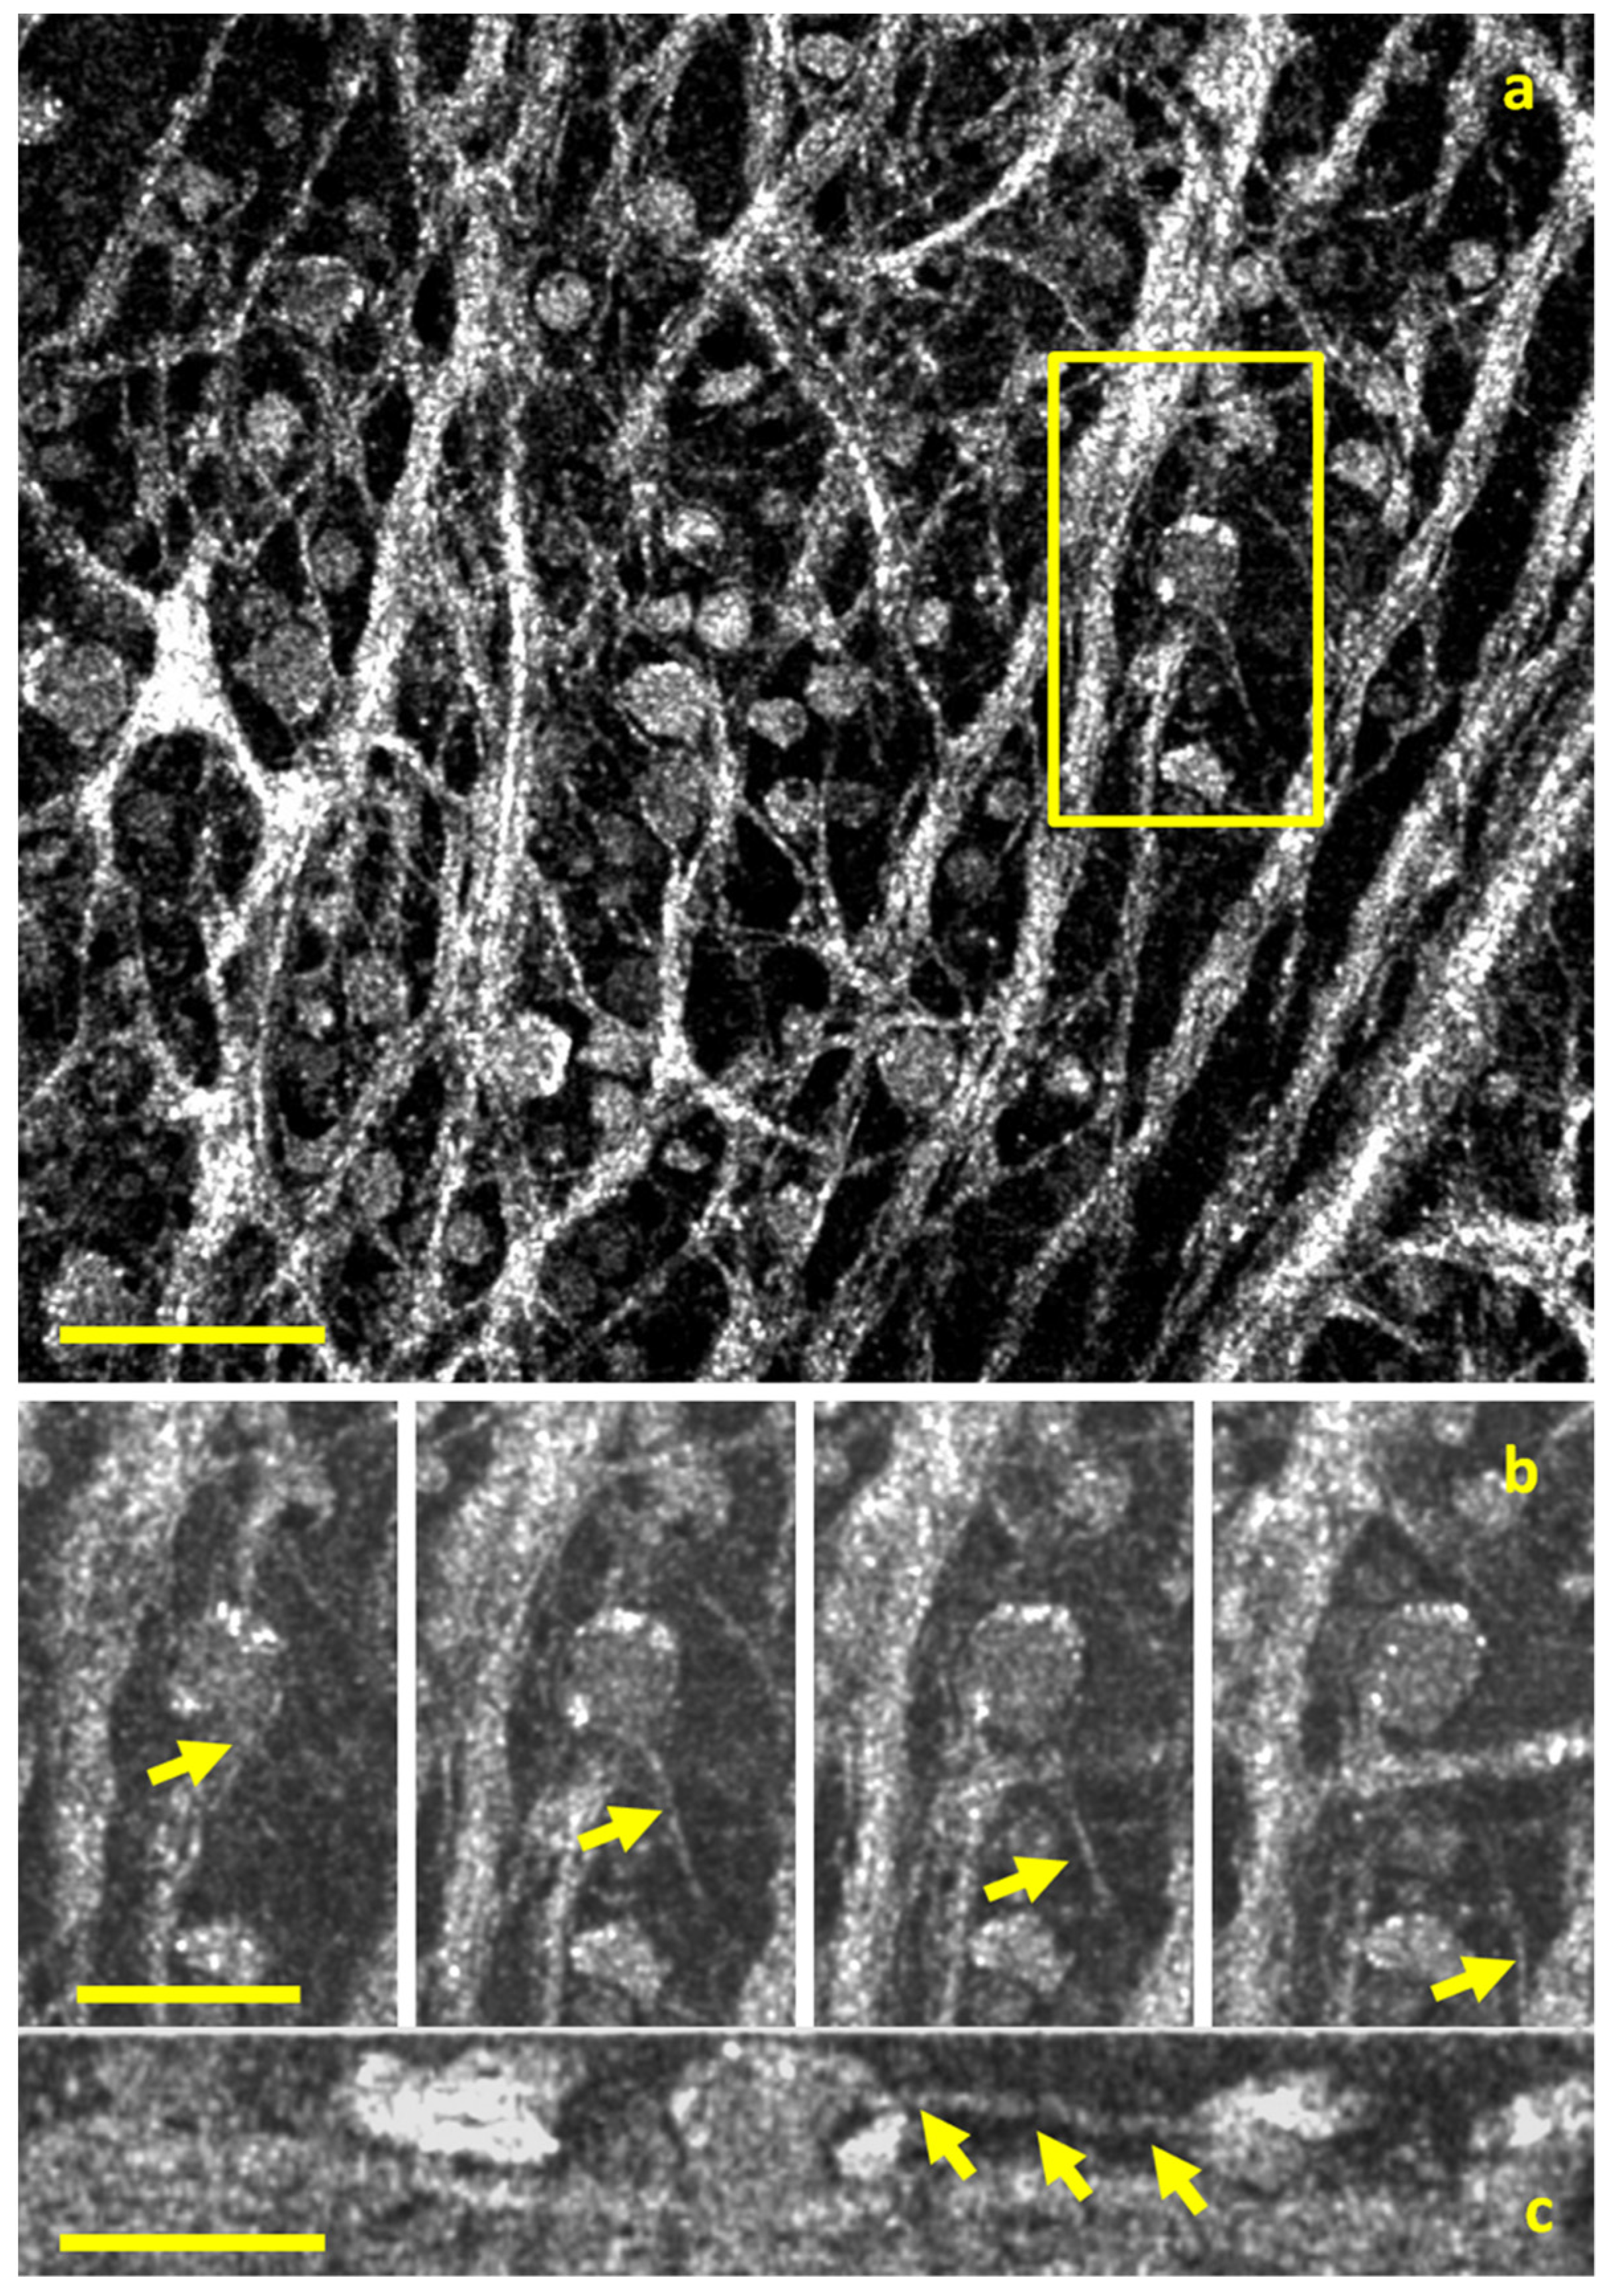

- Liu, Z.; Kurokawa, K.; Zhang, F.; Lee, J.J.; Miller, D.T. Imaging and quantifying ganglion cells and other transparent neurons in the living human retina. Proc. Natl. Acad. Sci. USA 2017, 114, 12803–12808. [Google Scholar] [CrossRef]

- Scholler, J.; Groux, K.; Goureau, O.; Sahel, J.A.; Fink, M.; Reichman, S.; Boccara, C.; Grieve, K. Dynamic full-field optical coherence tomography: 3D live-imaging of retinal organoids. Light Sci. Appl. 2020, 9, 140. [Google Scholar] [CrossRef] [PubMed]